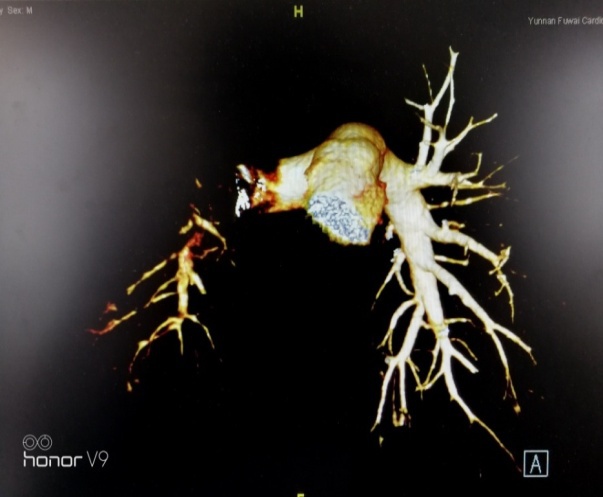

术后患者每日坚持服用抗凝药物治疗,2021年1月,患者感到活动后有胸闷,呼吸困难的问题。再次来到云南省阜外医院肺血管专科就诊。住院后V/Q肺通气血流灌注核素显像提示:左下肺血流与通气灌注不匹配,血栓高度可能。之后行右心漂浮导管与肺动脉造影发现:患者左下肺A6/A8/A9亚段分支以下有血栓形成。

.jpg)

随即再次与阜外医院肺血管中心柳志红主任联系,组织进行网络会诊。阜外医院肺血管中心柳志红主任、熊长明主任和赵智慧主任共同认为,患者为慢性血栓性肺动脉高压,内膜剥脱术后残余肺高压。可以采取内科微导管介入手术,肺动脉球囊扩张术(BPA)进一步改善患者心肺功能情况。